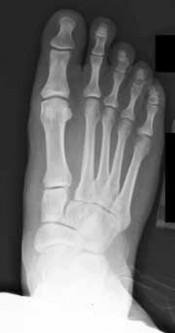

A 55-year-old woman presents with a symptomatic hallux valgus deformity. Weight-bearing radiographs demonstrate a hallux valgus angle (HVA) of 42 degrees, an intermetatarsal angle (IMA) of 16 degrees, and clinical hypermobility of the first tarsometatarsal (TMT) joint. What is the most appropriate surgical intervention?

Correct Answer: First TMT joint arthrodesis (Lapidus procedure)

Explanation:

A first tarsometatarsal (TMT) joint arthrodesis, also known as a Lapidus procedure, is indicated for moderate to severe hallux valgus deformities (IMA > 15 degrees) that are accompanied by hypermobility of the first ray. It corrects the deformity at the apex (the TMT joint) and provides stability. A distal chevron is for mild deformities without hypermobility.